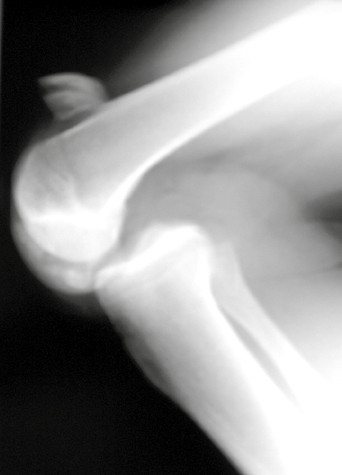

Zur quantitativen Erfassung der posterioren tibialen Translation haben sich gehaltene Röntgenaufnahmen bewährt (Abb. 4). Die posteriore tibiale Translation wird in diesen Aufnahmen im Vergleich zur Gegenseite am seitlichen Röntgenbild in Millimetern bestimmt. Ab einer posterioren Translation von 5 mm im Vergleich zur Gegenseite spricht man von einer „hinteren Instabilität“. Ab 12 mm besteht der Verdacht auf eine Begleitverletzung der posterolateralen oder posteromedialen Strukturen 33 34. Auch die Applikation einer nach anterior gerichteten Kraft hat in der Diagnostik hinterer Instabilitäten eine Bedeutung, da auf diese Weise eine fixierte hintere Schublade ausgeschlossen werden kann 35. Von einer fixierten hinteren Schublade spricht man, wenn trotz anterior gerichteter Kraft eine posteriore tibiale Translation besteht (Abb. 5). Liegt eine fixierte hintere Schublade vor, so muss diese vor einer operativen Rekonstruktion erst behandelt werden, sonst kann das Knie durch die ligamentäre Rekonstruktion nicht in die Neutralstellung gebracht werden. Hier hat sich die konservative Therapie mit einem „posterior tibial support brace“ bewährt (PTS Brace, Medi, Bayreuth).